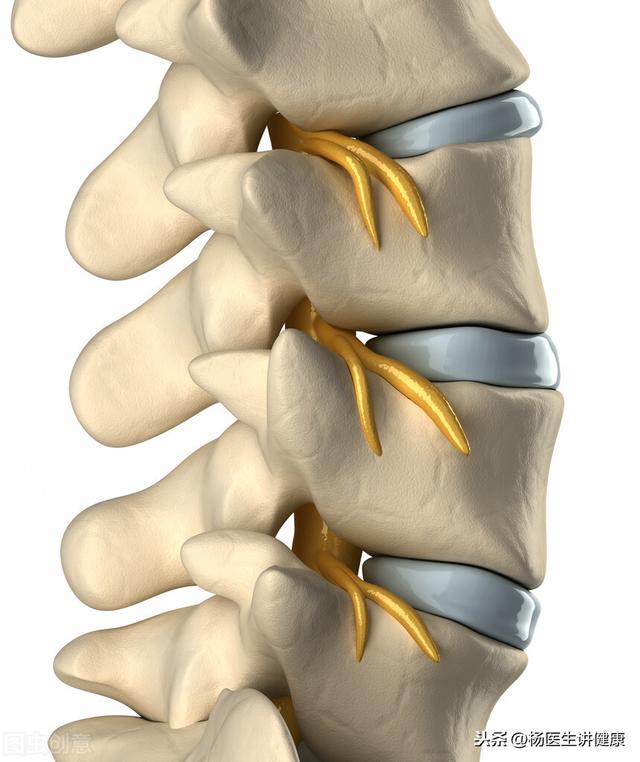

この私たちの体を支える1本の骨が背骨である。背骨は頸椎、胸椎、腰椎、仙椎に分けられる。背骨を構成する最も重要な構造は椎骨であり、椎骨は竹の節のように積み重なって背骨を形成している。正常な人の背骨は可動性が高く、腰椎と同様に首も左右に前後に振ることができる。胸椎と仙椎は比較的固定されている。

まず、人体の脊椎を見てみよう。脊椎とはよく言ったもので、人体の上部の重力を支える役割を担っている。横から見ると'ス'の形をしていて、上端と頭部がつながっていて、その次の7節が頸椎、その次の12節が胸椎、その次の5節が腰椎、その次が仙椎、尾椎と順番につながっている。動きやすくするために、椎骨は固定された単位ではなく、動くときに擦れ合わないように柔らかい椎間板でつながっており、この2枚目の椎間板を「椎間板」という。椎間板は運動や圧力によって変形し、はじめはある場所に圧力がかかると外側に膨らみ、椎間板の外側にある環状線維が破れて髄核があふれ出すと再び外側に膨らみ、椎間板の外に抜け出すことを「椎間板ヘルニア」といいます。頚椎における椎間板ヘルニアの発生率は低く、頚椎症は姿勢の悪さによるものがほとんどで、弯曲がまっすぐになったり、後弯したりすることが多い。脳脊椎では、胸郭が補強されているため、椎間板ヘルニアは起こりにくい。では、質問でしっかり出ている椎間板はというと、腰椎椎間板ヘルニアを指しているのですが、確かに腰椎は上半身の圧力に耐える部分が大きく、周りに補強するものがなく、さらに生業の姿勢が悪いので、腰椎椎間板ヘルニアになりやすいのです。腰椎椎間板ヘルニアは、腰や足に痛みやしびれを感じると、病気の根源は、椎間板の突出、周囲の神経根の圧迫と病気によって引き起こされ、病気を排除するために、血液の活性化のための伝統的な漢方薬だけで、経絡とチャネルを調整し、神経根の圧力はもはや圧縮されないように、病気は排出することができます。そして、一部の人々は、閉鎖注射で、痛みやしびれの症状を緩和するために、知らない、これは '喉の渇きを癒すためにヘムロックを飲む'です。同時に、閉鎖注射はまた、寿命を短縮し、使用すべきではありません!漢方薬は奥が深く、多くの凝縮困難な雑多な病気は、ガラスを攻撃するために漢方薬である。